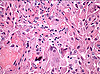

Caso 1.Paciente homem, 41 anos, lesão em cavidade oral

Paciente homem, 36 anos, tumor em mucosa jugal há 3 anos.

Paciente homem, 22 anos, tumor em parótida com duas recidivas anteriores.